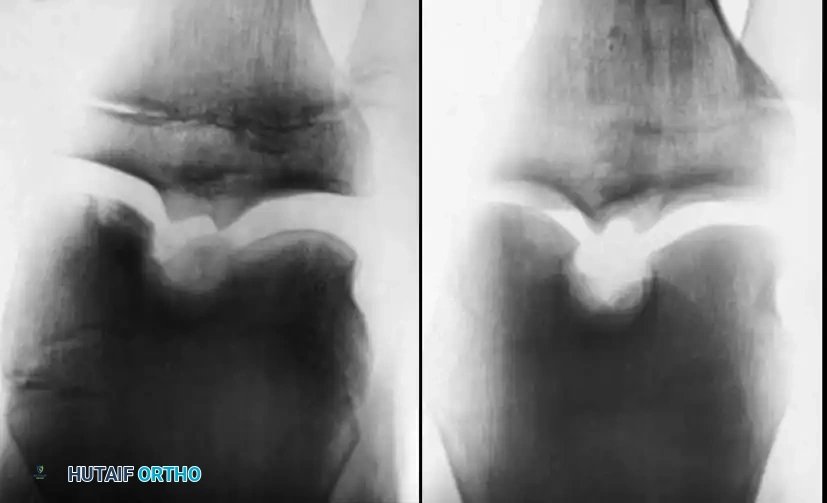

Standard radiographic evaluation is the first-line diagnostic modality. A complete knee series must include weight-bearing anteroposterior (AP), lateral, skyline (patellar), and tunnel (intercondylar notch) views.

Surgical Warning: Because the most common location for an OCD lesion is the posterolateral aspect of the medial femoral condyle, standard AP views may obscure the defect. The tunnel view (flexed knee posteroanterior radiograph) is absolutely critical for visualizing these lesions.

Comparison radiographs of the contralateral knee are highly recommended in juvenile and adolescent patients. OCD is bilateral in approximately 30% of patients, and comparison views help differentiate true OCD from bilateral anomalous ossification centers, which typically resolve spontaneously within 6 to 12 months.